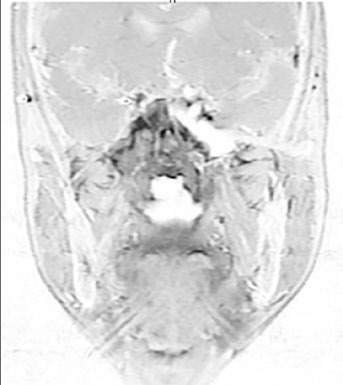

Caso 2: T4N2 EBV positivo

Paciente con enfermedad localmente avanzada, extensión intracraneal a través del foramen oval y seno cavernoso ipsilateral, adenopatías bilaterales en niveles II-V. El GTV70 incluyó el tumor primario con toda su extensión intracraneal visible en RM T1 con gadolinio, así como el conglomerado ganglionar necrótico. El CTV70 se expandió 5 mm en la mayoría de las direcciones, reduciéndose a 0 mm en la interfaz con el lóbulo temporal. El CTV subclínico requirió la inclusión del seno esfenoidal completo, el clivus completo, la cavidad de Meckel bilateral y todos los niveles cervicales bilaterales hasta la grasa posterior a la clavícula en el nivel V.

Ambos casos fueron tratados con quimiorradioterapia concurrente con cisplatino, esquema SIB en 33 fracciones (70 Gy al PTV70, 56 Gy al PTV56), con verificación mediante CBCT diario.